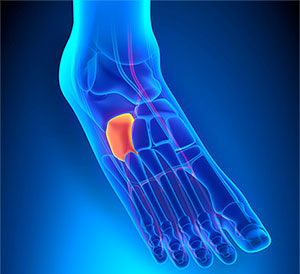

● 骰狀骨症候群cuboid syndrome

(圖解)骰狀骨為腳踝七塊骨頭之一,位於外側;骰狀骨症候群多發生在過度使用或反覆扭傷後,骰狀骨產生半脫位,造成個案於承重或步行時會疼痛。